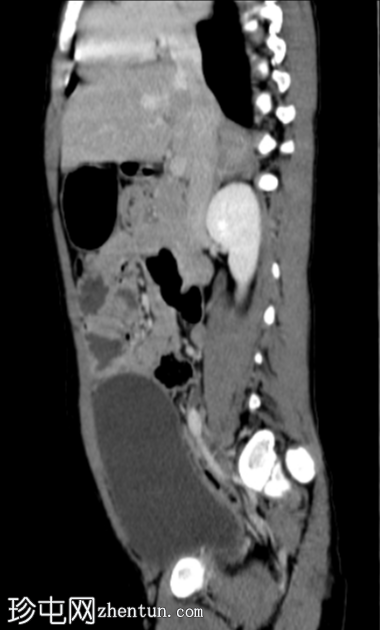

轴位

平扫

阑尾过长,跨越中线向左侧延伸。阑尾呈扩张状态,充满液体(8mm),管壁增厚并强化,近端可见多发性穿孔。阑尾周围脂肪间隙模糊,可见液体密度影和管腔外气体。未见脓肿。